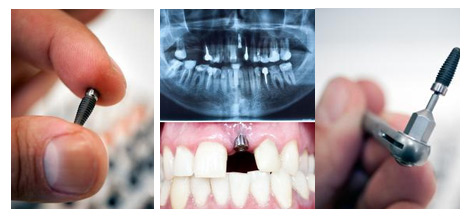

种植牙可以用多久

发布日期:2018-04-13 来源:沈阳康贝佳口腔在关心种植牙寿命之前,想必我们多多少少都了解过种植牙,也知道它的价格并不是像补个牙,种植牙的价格一般在几千到几万元左右,这对于我们来说,也是一笔不小的开支,那我花了那么多钱,到底这个牙能用多长时间呢?我们跟随康贝佳口腔的医生一起来看一下。

康贝佳植牙医生介绍说,种植牙技术已经发展成熟,但种植的牙齿是需要定期检查和维护的,只要后期维护得当,一颗高质量的种植牙能使用几十年,甚至。1965年,第一例种植牙在瑞典诞生,为缺牙者服务超过40年。种植牙寿命主要与以下因素有关: